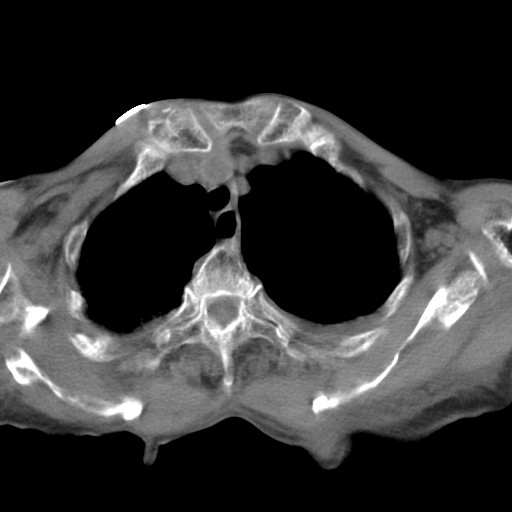

女,93岁,摔伤后检查。

右肩甲骨粉碎性骨折,上传骨窗

右侧锁骨\\肩胛骨骨折、右侧湿肺,心功能不全伴双侧胸腔积液,右下肺膨胀不全,左膈破裂或食管裂孔疝,冠脉钙化,心包少量积液,请上传骨窗.

右肺炎症,心功能不全伴双侧胸腔积液,右下肺膨胀不全,食管裂孔疝,冠脉钙化,心包少量积液,左侧肋骨骨折,右肩甲骨粉碎性骨折。93岁,高寿哇!

右肺炎症,心功能不全伴双侧胸腔积液,右下肺膨胀不全,食管裂孔疝,冠脉钙化,心包少量积液,左侧肋骨骨折,右肩甲骨粉碎性骨折。